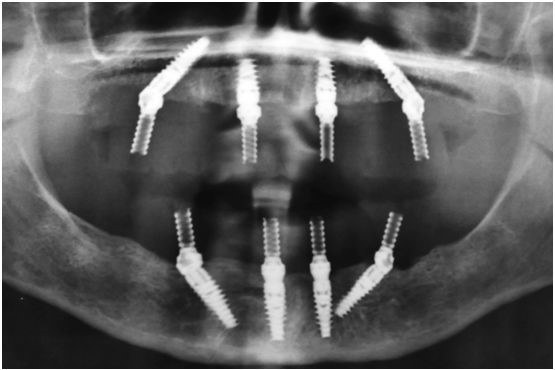

Рентген имплантов Alpha Bio: диагностика и качество